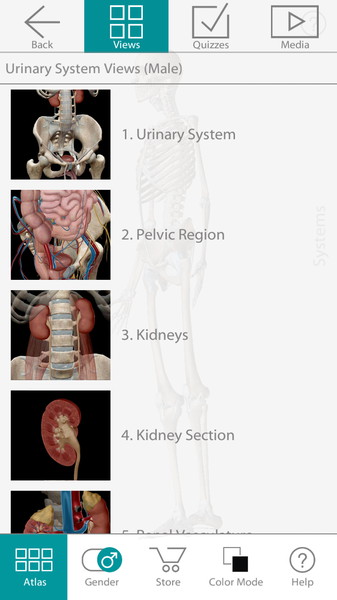

Трехмерный атлас по анатомии рассматривает модели мужской и женской анатомии. Для этого достаточно будет выбрать F или M. Далее воспользуйтесь удобным поиском по системам (Select System) и Вы сможете рассмотреть любое сочетание анатомических образований на черном или белом фоне, прочитать и услышать их полное описание (положение, форму, функциональные и физиологические особенности). Приложение само по себе очень чувствительно. Удивительно то, что при максимальном увеличении изображение не теряет своей детализации. Пользователь в полной мере сможет воспользоваться жестами многозадачности и понимание строения человека будет максимально эффективным.

- Рассматриваются полноценные модели как мужской, так и женской анатомии.

- Каждая модель содержит порядка 4600 анатомических образований.